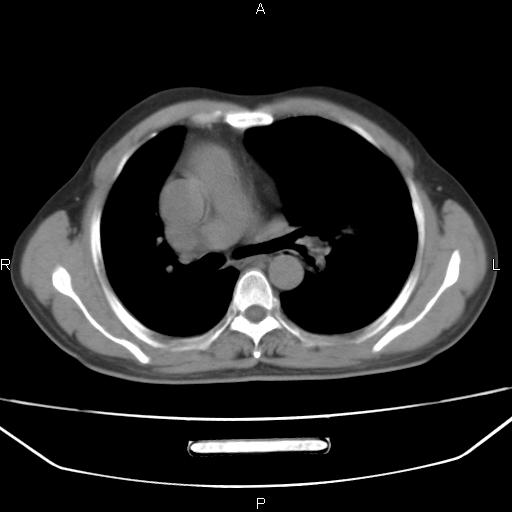

患者,男。50岁。近几日有咳嗽症状,无其他不适,既往病史无,考虑膈疝。请前辈们看看指导指导。

膈膨升,左下肺通气不良,膈肌好像还完整。

考虑左侧膈疝。

左侧膈疝。

符合隔膨升,膈肌较完整。